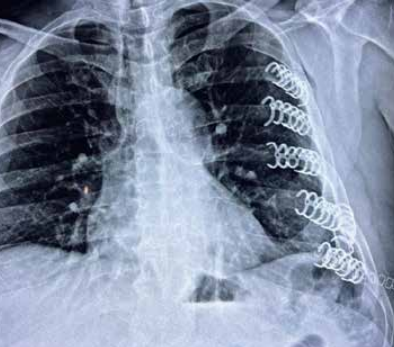

En nuestro medio, desafortunadamente, es cada día más frecuente el trauma cerrado de tórax relacionado a accidentes por vehículos de motor y en segundo lugar los relacionados a caídas. En estas situaciones son frecuentes las fracturas costales, el colapso pulmonar, llamado neumotórax y el derrame pleural, llamado hemotórax.

En estas situaciones los que se requiere dependiendo de la gravedad de la situación es drenar la cavidad pleural del aire o líquido que se acumula por el golpe y en caso de presentar fracturas costales, fijarlas con clips de titanio diseñados para que la fractura sane más rápido y con menos dolor.